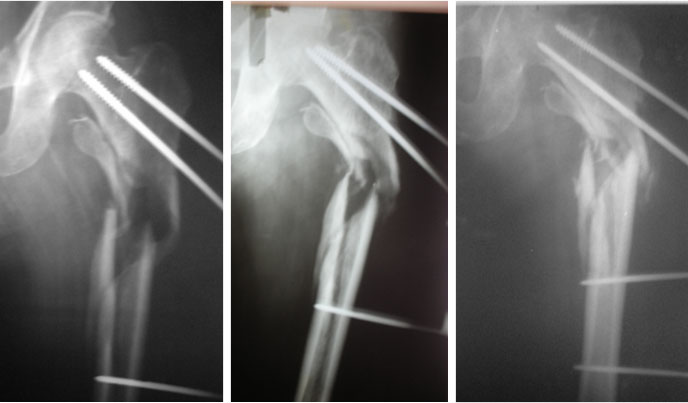

2008

He now had an infected stiff nonunion. Discharging sinus, pain and limp.

2009

Again operated for the same, this time fixed with locking plate and dynamic hip screw.